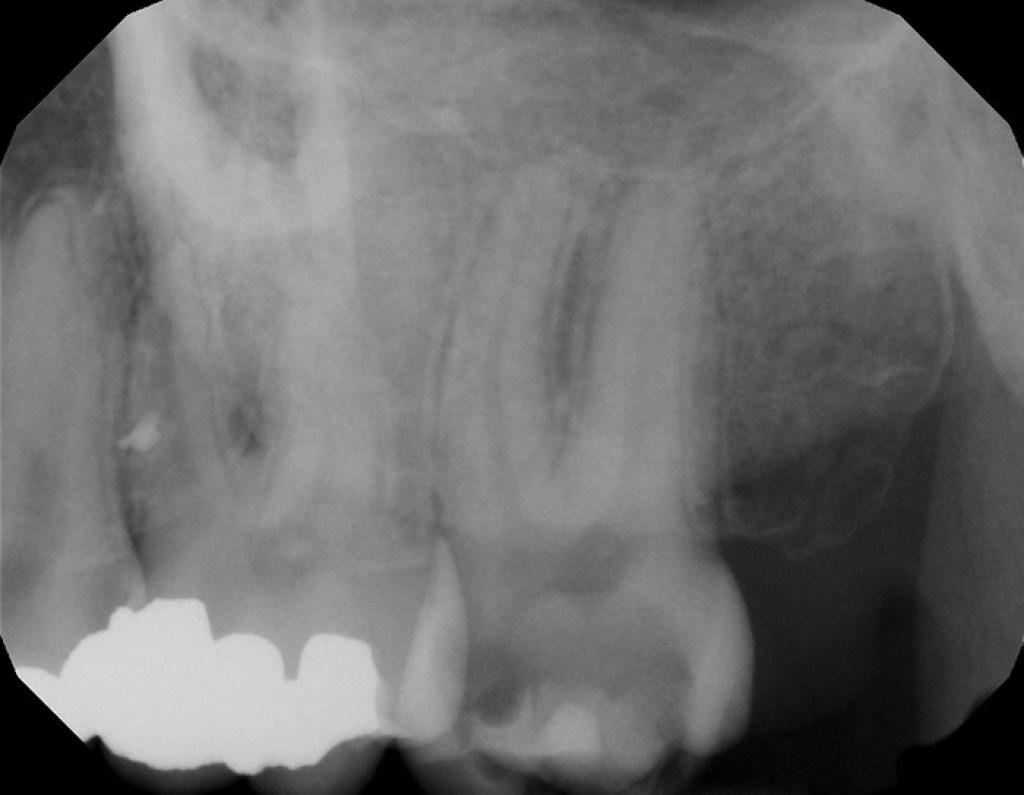

Dx: Pulpal Necrosis with SAP

Dx: Previously Treated with CAA